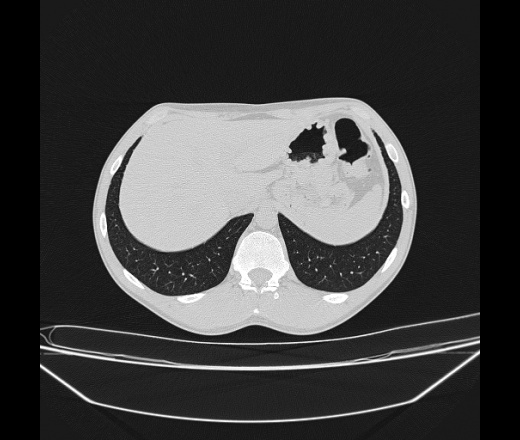

Молодой парень 18 лет, призывник, при прохождении ФЛС на верхушек левого легкого выявили очаги средней интснисвности с нечеткими контурами, тяжи. Сделали бок и томограммы 6-7-8. Везде описывают как очаговый твс. Вижу только перибронхиальный фиброз. Что за изменения в бронхах, указано нижи стрелками, тоже перибронхиальный?

Не стал бы говорить об очагах. Акцентировал бы не на фиброзе, а на тракционных бронхоэктазах. Не обязательно они результат tbc бронхов, но проверить не помешает.

Иван, пациент ведь уже "направлен с ОПТД", так?surprise Возвращайте его назад с заключением о возможном микобактериозе. Остаточные поствоспалительные ( посттуберкулёзные?) в дифряд.Очаговый твс с неясной активностью они уже себе "нарисовали", как я поняла.

+1 за микобактериоз.